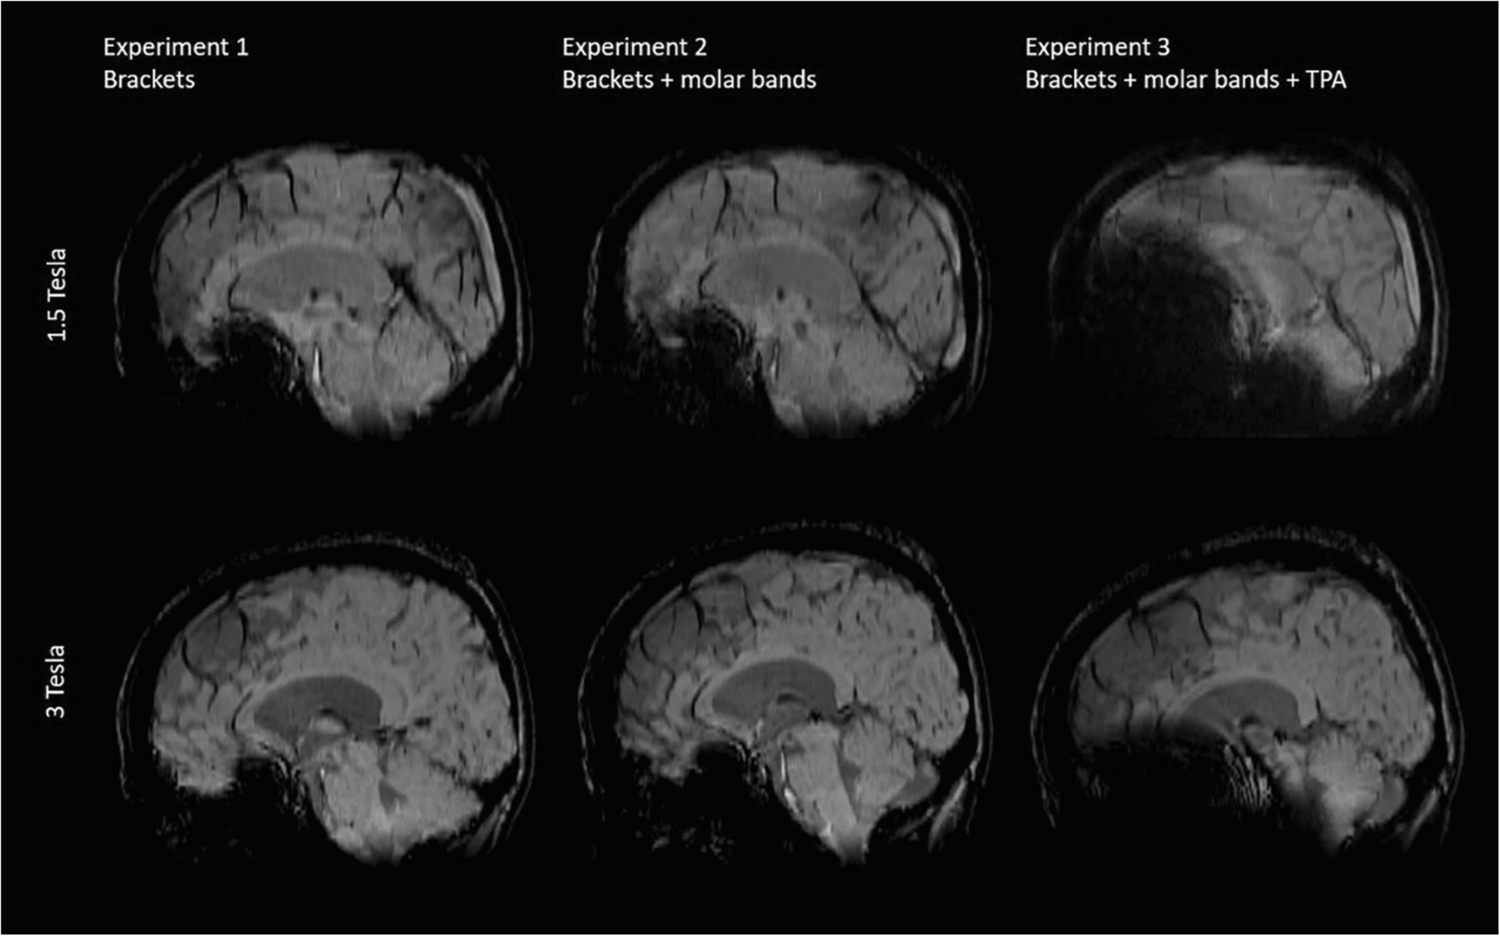

The strongest artifacts are observed in SWI as shown in Figs. 2 and 3, respectively.

Fig. 2

Comparison of representative slices of an axial SWI image from all three volunteer Experiments acquired at 1.5T and 3T

Bild vergrößern

Fig. 3

Comparison of representative slices of a reconstructed sagittal SWI image from all three volunteer Experiments acquired at 1.5T and 3T